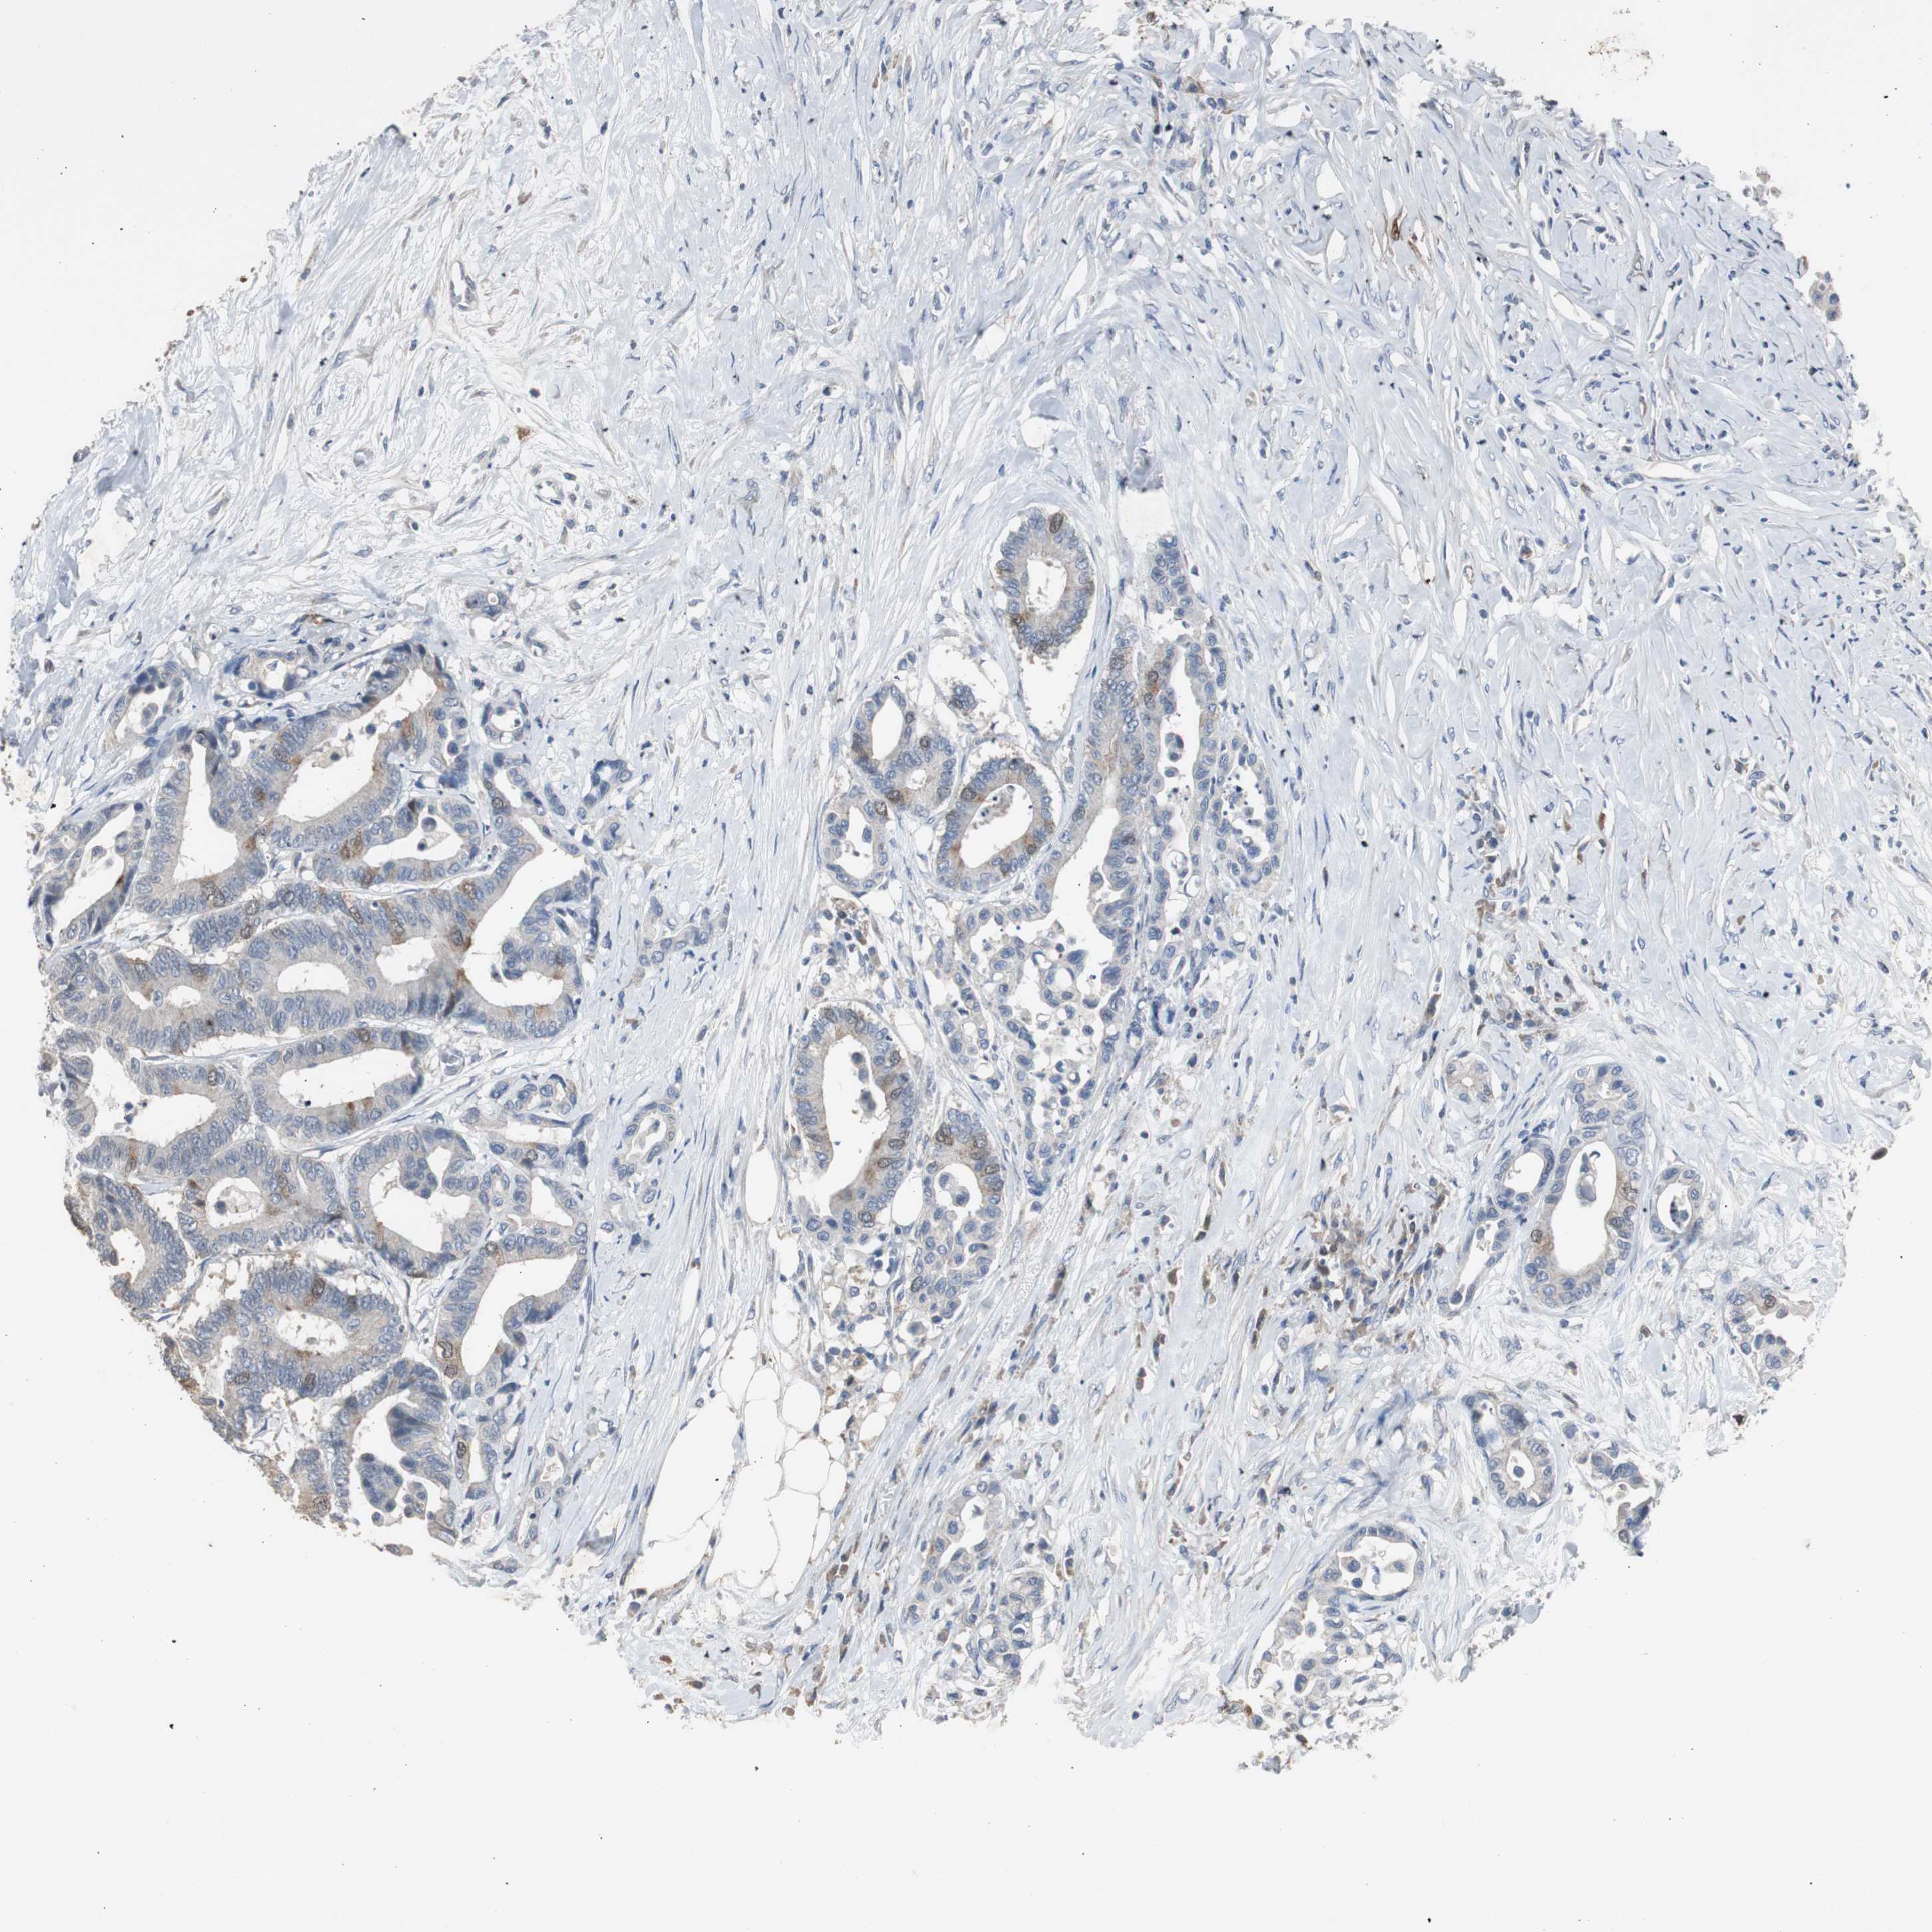

ANTIBODIES

AND

VALIDATION